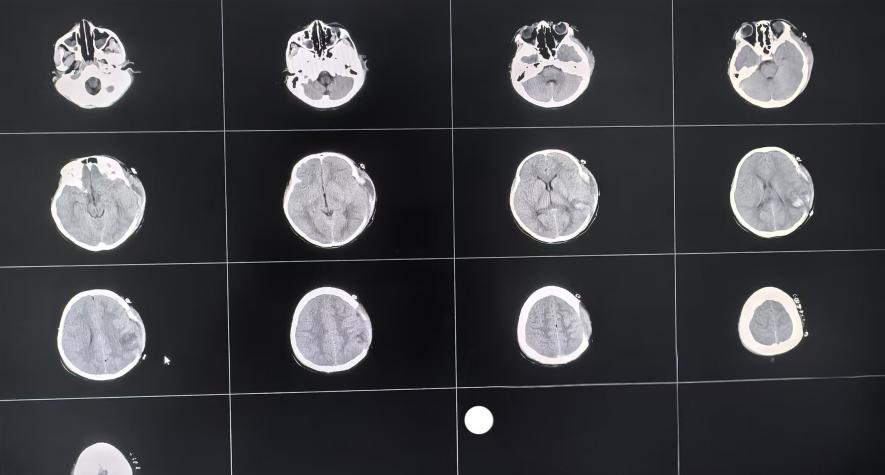

一名10岁女童,因外伤致意识不清呈昏迷状态近2小时,一侧瞳孔散大,被送往我院急诊医学科,神经外科一病区刘如欲主治医师在接到会诊申请后,迅速前往急诊医学科参与救治。经颅脑CT检查提示:患儿左侧颞顶骨骨折,部分断端刺入脑内,左侧颞顶部硬膜下血肿,左侧颞顶叶挫裂伤并血肿形成,弥漫性脑肿胀,脑干损伤,脑疝形成。刘如欲主治医师第一时间将检查结果上报,马小红主任团队综合评估后,考虑到患儿脑疝形成,弥漫性脑肿胀,病情危重,需立即进行手术。经与患儿家属充分沟通后,决定为其行左侧颅内血肿清除+去骨瓣减压术。

术前颅脑CT图

术后颅脑CT图